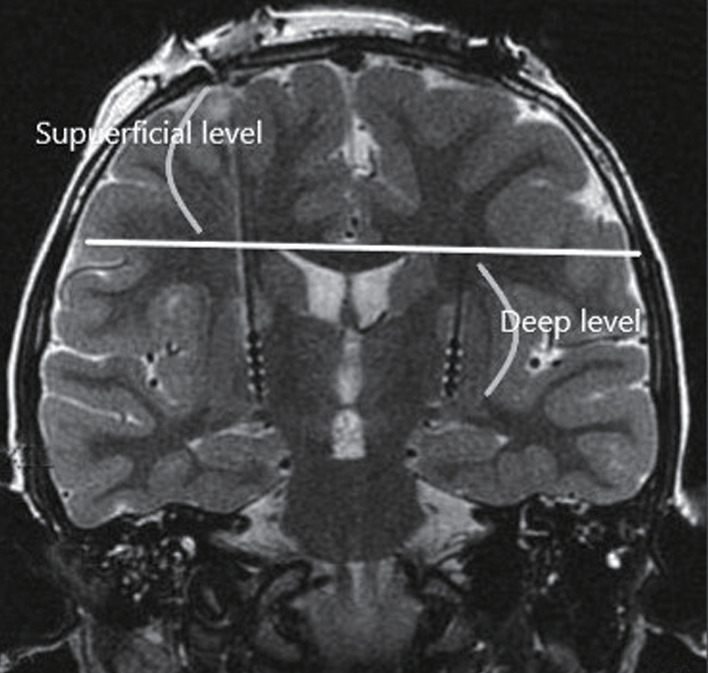

Methods: We conducted a retrospective review of patients who underwent DBS at a single institution from September 2018 to February 2023. Surgical planning data were analyzed using a combination of 1.5 Tesla (T) and 3.0 T magnetic resonance image (MRI) for trajectory planning. Trajectories were classified into four types (type 1-4) based on the proximity of vascular structures within 2 mm on preoperative MRI scans, as defined in this study. Hemorrhage presence was evaluated through postoperative computed tomography scans.

Results: Out of 200 patients analyzed, type 1 trajectories (no vascular structures within 2 mm on both MRIs) accounted for 72.70% of cases with the lowest hemorrhage rate. Significant differences in hemorrhage rates were observed among the types, with higher risks associated with type 4 trajectories. Additionally, significant variations in vascular structure types were noted across DBS targets, with subthalamic nucleus showing the highest risk.